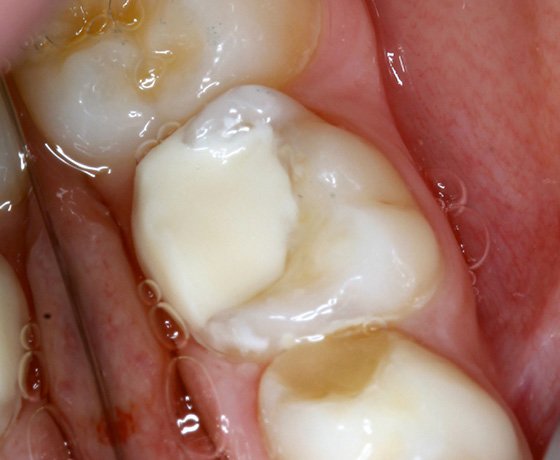

Isolation was obtained with low volume suction, cotton rolls and adult matrix band to decrease the incidence of saliva contamination.

Pre-op situation with reduced saliva.